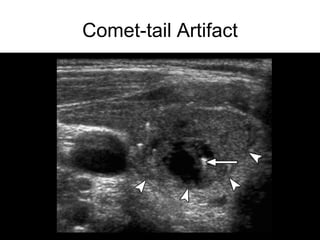

• Comet-tail

Comet-tail Artifact

Ultrasound • Hypoechoic • Increasedcentral vascularity • Incomplete halo • Microcalcifications • Irregular borders • Taller than wide (transverse view) • Suspicious lymph nodes • Hyperechoic • Peripheral vascularity • Complete Halo • Comet-tail • Large, coarse calcifications High Risk Features Low Risk Features